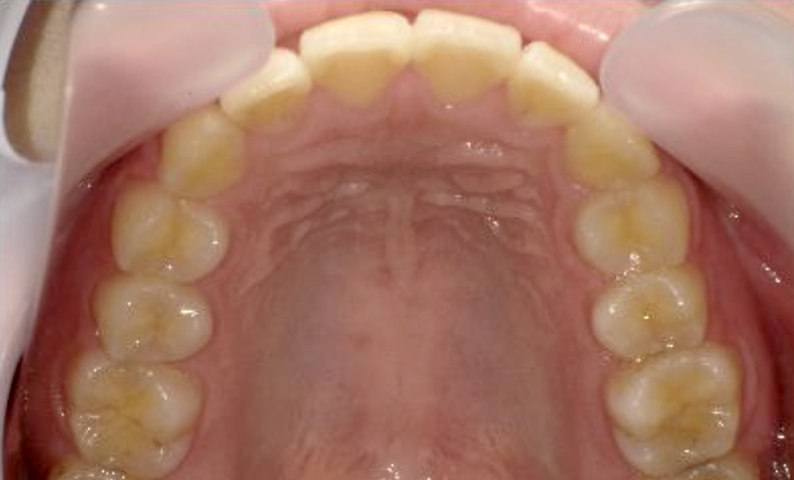

症例_025 上顎だけの部分矯正

治療期間:7ヶ月金額:30万円+税女性前歯のガタガタ上の前歯だけ

| Before | After |